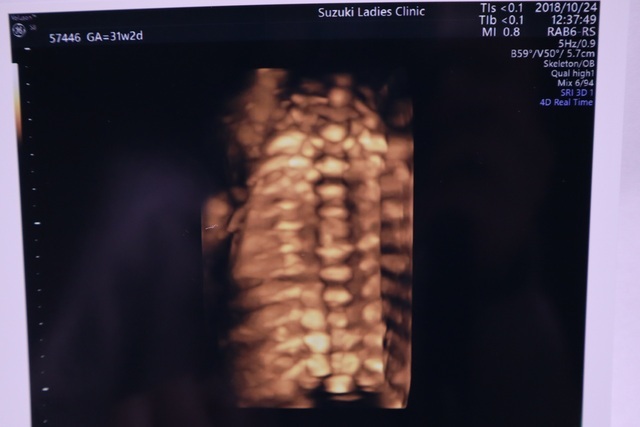

31週2日(31w2d・女の子)|mkmkmkmk さん(23歳)

エコー写真撮影時のエピソード:

初めて背中のエコーを撮ってもらった時はなんて綺麗な背骨!って大はしゃぎしてたけど4週連続背中のエコー...

背中はもういいから顔を見せておくれ(笑)